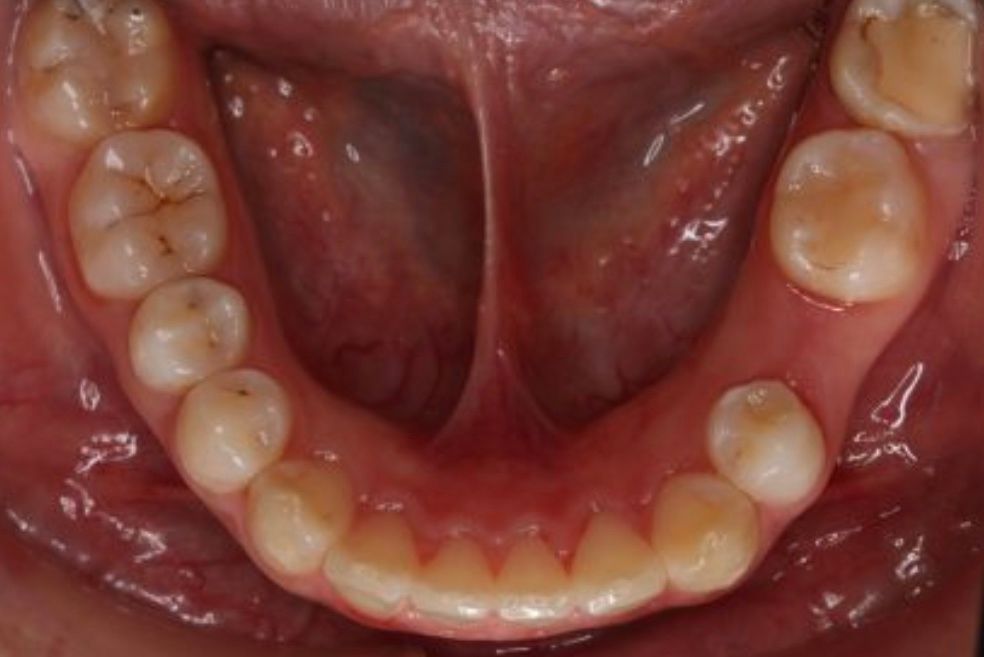

Fotos y videos